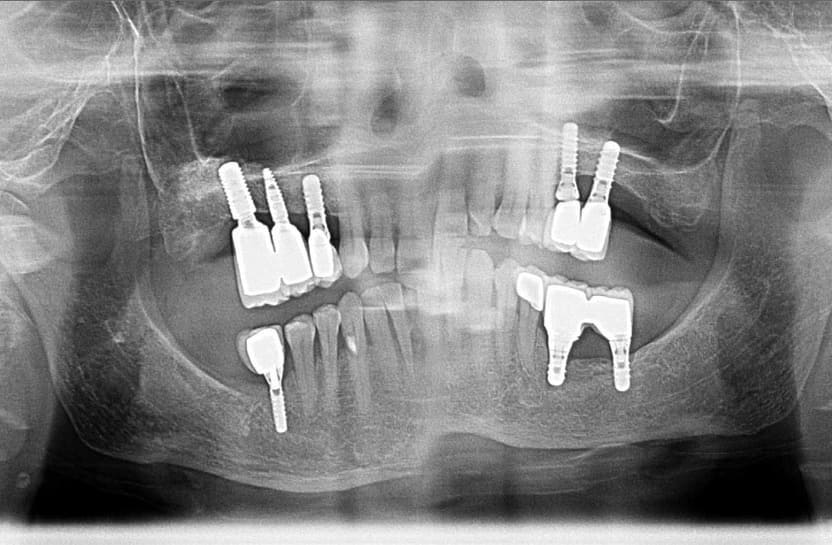

Dental Implant

İmplant eksik dişleri tamamlamak için çene kemiğine yerleştirilen bir tür vidadır. Bu vidalar titanyum adı verilen doku dostu bir materyalden imal edilir. Titanyumun doku ile uyumu ve kemiğe bağlanması çok iyidir. Yerleştirildikten sonra vücudun bir parçası haline gelir ve maksimum dayanıklılık gösterir.